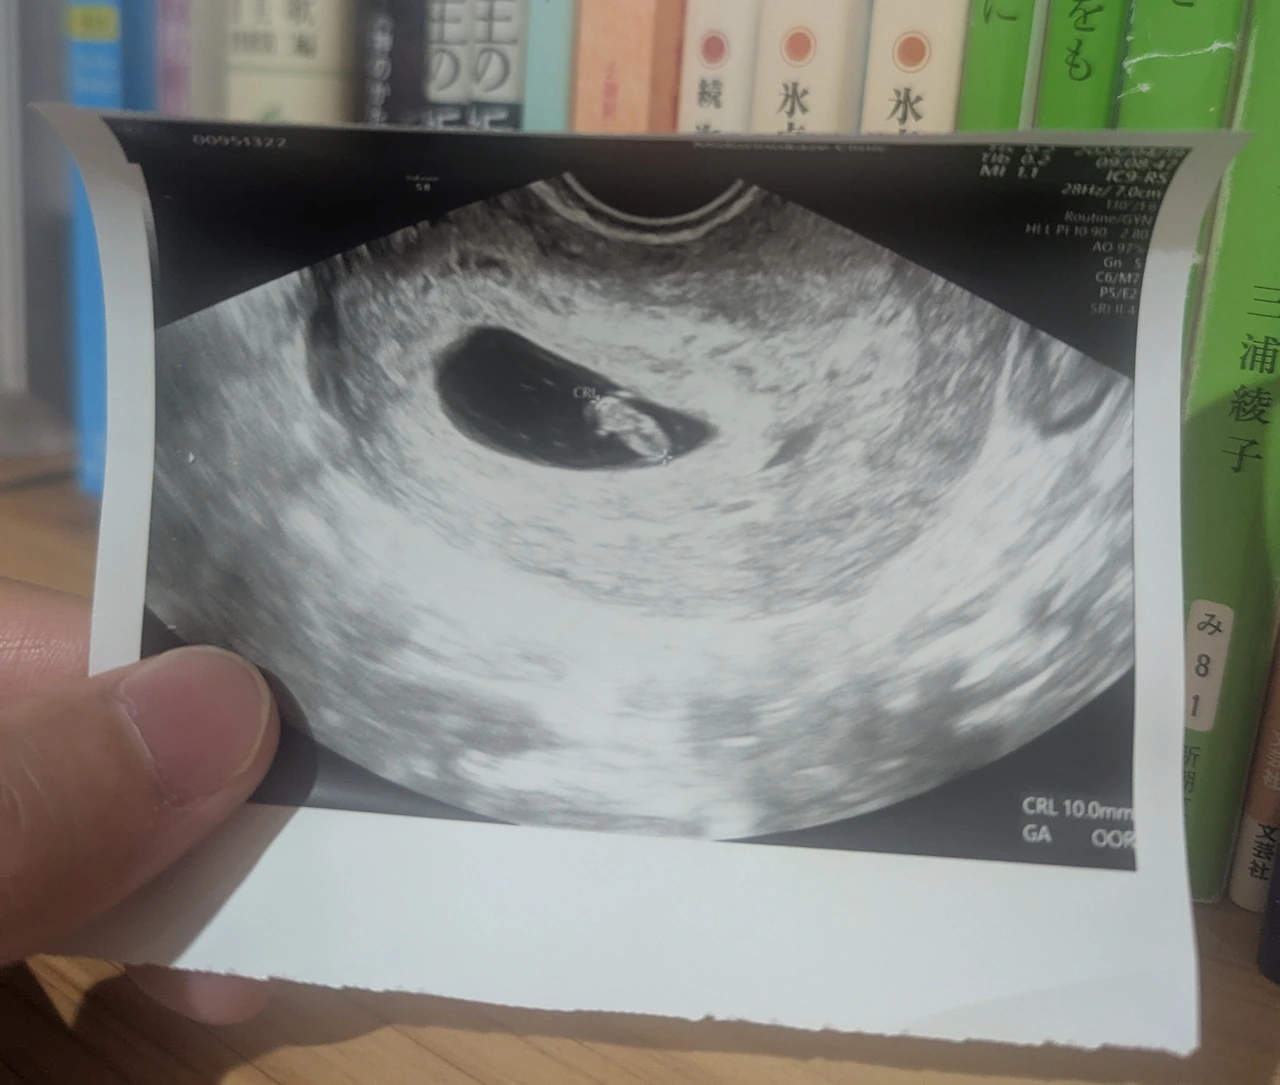

예정에 없던 선물,

'셋째'가 생겼습니다.

기쁜 소식

태어날 아이를 기다리는 마음이 담긴

따뜻한 하이쿠와 함께 전해 드립니다.